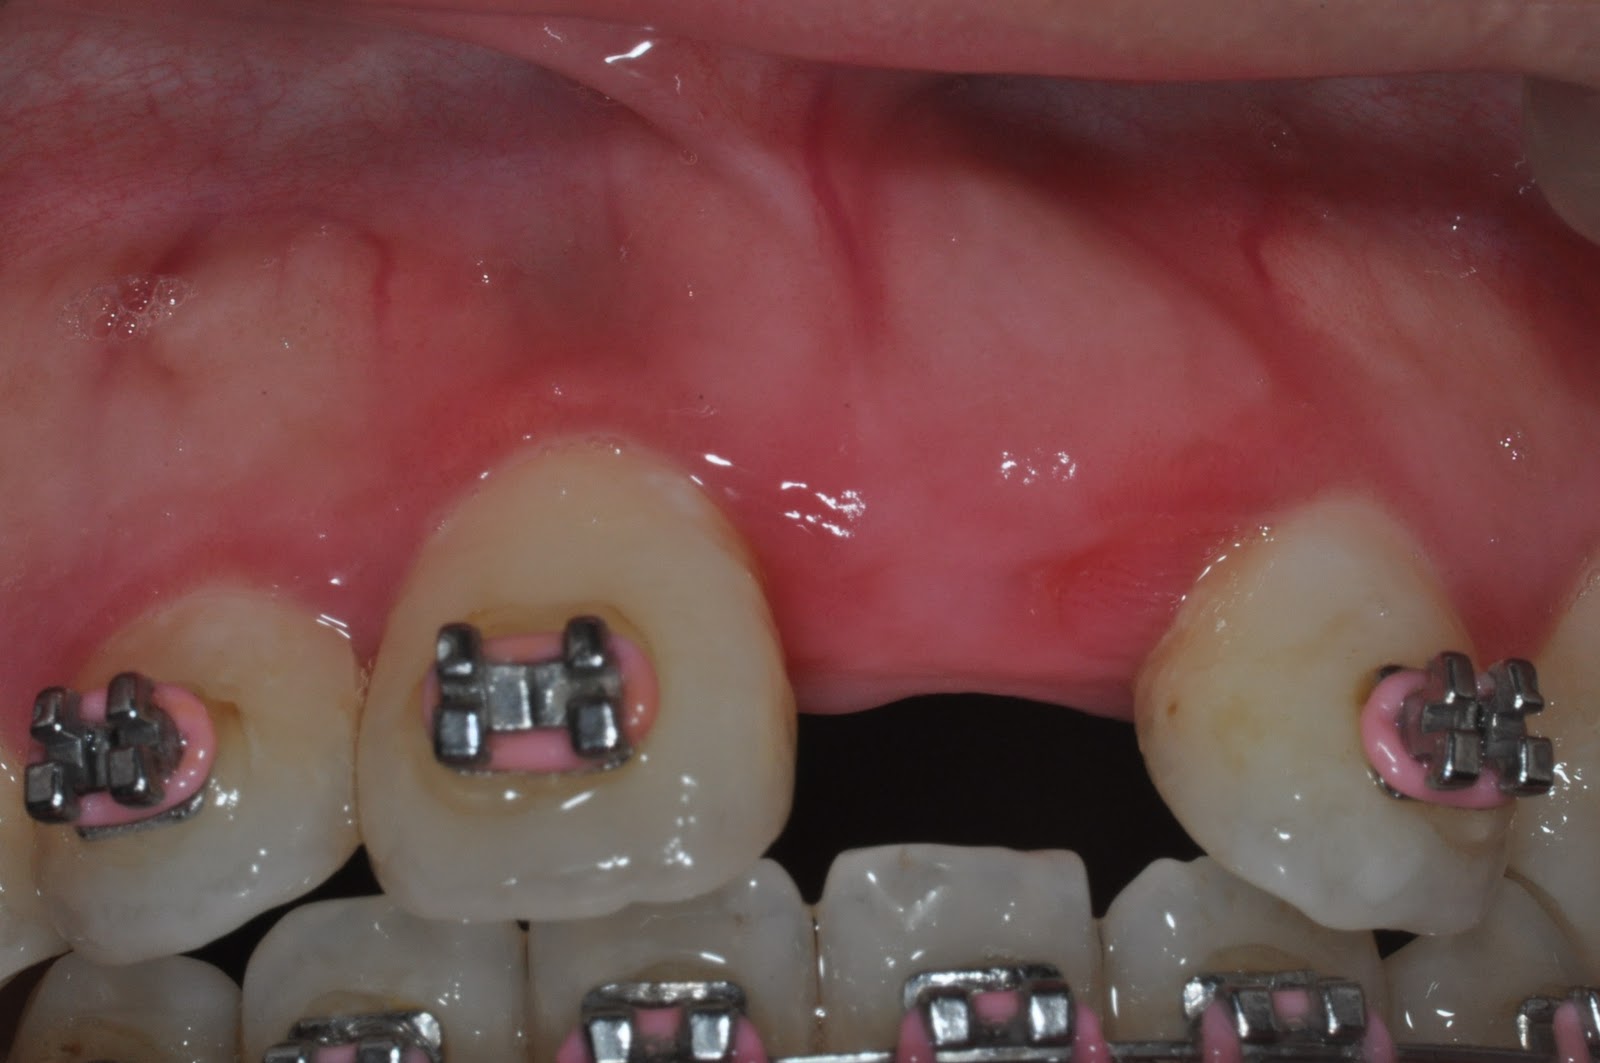

VISTA for single upper anterior tooth + GBR

Pre-OP

Osseous defects

Final restoration(2012.07.27)